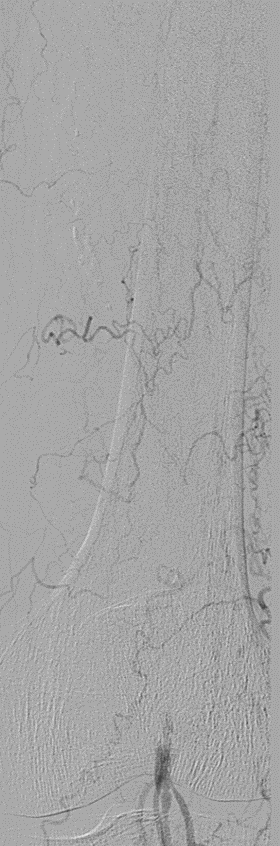

★ Case 1

noproximal stump in SFA,>250mm

★ Case 2

significantdistal collaterals